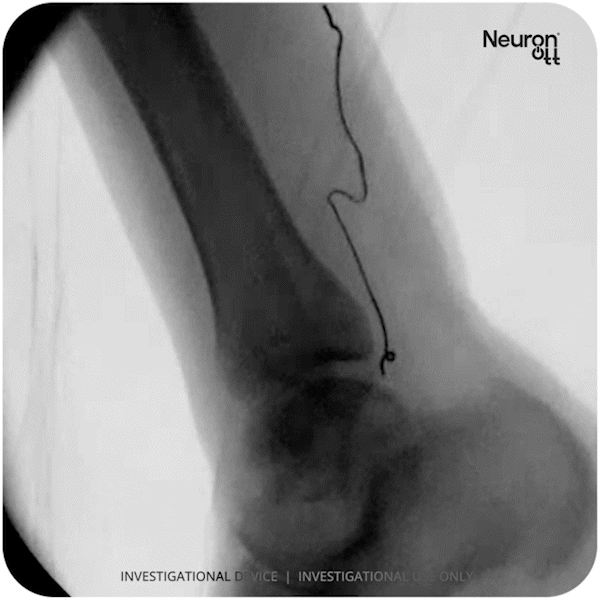

Injectrode on Tibial Nerve in human pre-clinical study. Self-anchoring and flexibility of the chronic lead enables better long-term reliability as the device moves and flexes with the tissue.

The DOD funding will support a clinical randomized controlled trial in collaboration with the University of Texas Health Science Center in Houston, TX. This three-year clinical evaluation, titled "Home Neuromodulation for Neurogenic Bladder Management in Spinal Cord Injury: A Hybrid Implementation-Effectiveness Trial," will assess the Injectrode's safety and efficacy when implanted along the tibial nerve in individuals with Spinal Cord Injury (SCI).

The study introduces Injectrode Tibial Nerve Stimulation (iTNS), evaluating its implantation process, measuring treatment effects through an 8-week self-administered protocol versus sham treatment, and investigating its mechanisms of action. Using the Injectrode as the active intervention, the study will measure both the complete elimination of overactive bladder (OAB) medication and the percentage reduction in OAB medications from baseline to study completion. As the first-in-SCI human clinical trial, this phase 1/2 study will provide crucial data for FDA presubmission engagements and inform the design of subsequent pivotal trials.